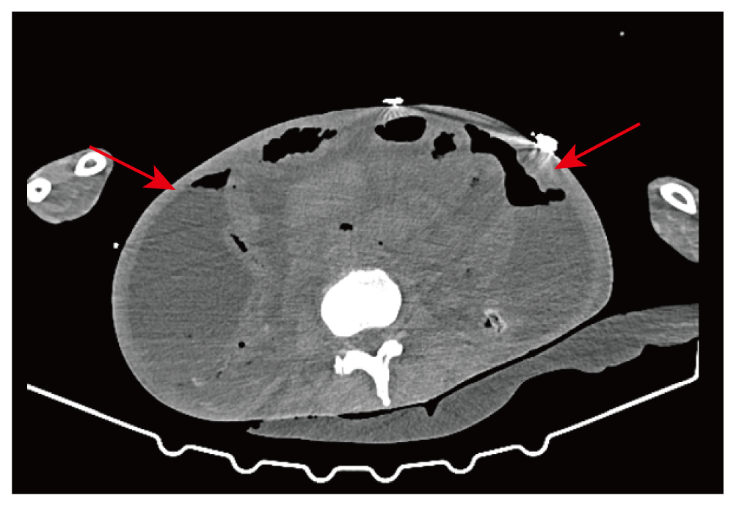

图1 2021年12月15日腹部CT平扫

注:图1示患者肠道扩张明显、积气积液,提示肠梗阻可能

肠梗阻;